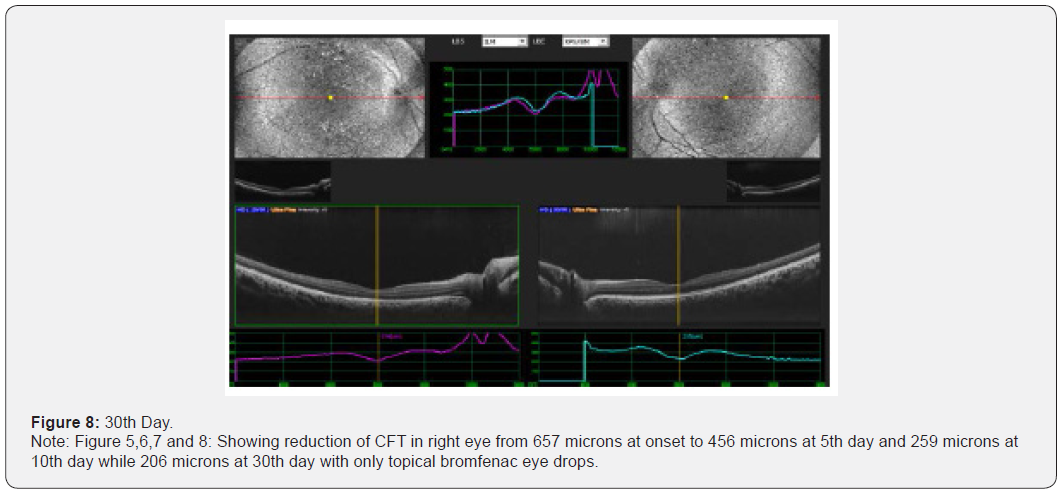

Results: This interventional study includes 21 patients who were diagnosed as acute CSC and followed from the day of presentation to 30th day. All 21 patients were undergoing intervention by using topical bromfenac eye drop, one drop twice daily for 30 days. Macular thickness and visual acuity recorded from the day of presentation up to 30th day. (Table 6) shows all changes before and after treatment and (Figure 1-4) shows early resolution of sub-macular fluid in one of these patients treated with topical bromfenac eye drops (one drop twice daily). In group 1 the macular thickness (CFT) improve from 422-485 microns at onset to 317-382 microns on 5th day becomes 246-295 on 10th day while 210-226 on 30th day. Vision improved from 0.4 to 0.7 at 5th day, improved to 0.8 on 10th day and remained same on 30th day. In group 2 the CFT reduced from 535-565 microns to 401-440 microns on 5th day becomes 318310 on 10th day and on 30th day it was 221-232 microns with improvement in visual acuity which was 0.2 at onset to 0.6 at 5th day, 0.7 at 10th day and improved to 0.8 on 30th day. In group 3 the CFT reduced from 657-722 microns to 456-469 microns on 5th day, 259-366 microns on 10th day while 206-227 microns on 30th day. Visual acuity improved from CF at onset to 0.4 on 5th day, 0.6 on 10th day and improved to 0.7 on 30th day. Conclusion: This, simple, safe, affordable and easily available treatment modality in all parts of the world with early rehabilitation of acute CSC patients.

This interventional retrospective as well as prospective study includes 21 patients who were diagnosed as acute CSC and followed from the day of presentation to 30th day. All 21 patients were undergoing intervention by using topical bromfenac eye drop, one drop twice daily for 30 days. Macular thickness and visual acuity recorded from the day of presentation up to 30th day. (Table 6) shows all changes before and after treatment and (Figure 1-8) shows early resolution of sub-macular fluid in one of these patients treated with topical bromfenac eye drops (one drop twice daily). In group 1 the macular thickness (CFT) improve from 422-485 microns at onset to 317-382 microns on 5th day becomes 246-295 on 10th day while 210-226 on 30th day. Vision improved from 0.4 to 0.7 at 5th day, improved to 0.8 on 10th day and remained same on 30th day. In group 2 the CFT reduced from 535-565 microns to 401-440 microns on 5th day becomes 318-310 on 10th day and on 30th day it was 221-232 microns with improvement in visual acuity which was 0.2 at onset to 0.6 at 5th day, 0.7 at 10th day and improved to 0.8 on 30th day. In group 3 the CFT reduced from 657-722 microns to 456-469 microns on 5th day, 259-366 microns on 10th day while 206-227 microns on 30th day. Visual acuity improved from CF at onset to 0.4 on 5th day, 0.6 on 10th day and improved to 0.7 on 30th day.